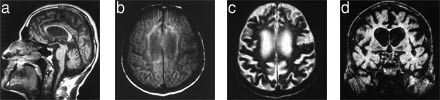

MR cerebrum viste utvidede ventrikler, grovt overflaterelieff og noe økt signalintensitet periventrikulært (fig 2). Skjelettrøntgen av hender og føtter viste cystiske oppklaringer i en rekke knokler (fig 3). Det var også mulig cystedanning i trochanterregionen og en usikker cystedanning i buen av C1. Det ble for øvrig ikke funnet cyster i aksialskjelett, dvs. cranium, columna, thorax og bekken. Ved histologisk undersøkelse av cystemateriale fra finger fant man et bilde som svarer godt til det som beskrives ved PLO-SL (fig 4). EEG viste abnorm aktivitet frontotemporalt bilateralt. Det var ingen epileptiform aktivitet. ”Brain stem auditory evoked response” (BAER) var unormal på venstre side, med ikke-reproduserbare potensialer ved repetert undersøkelse. Normal ”visual evoked response” (VER) og ”somatosensory evoked response” (SER). I spinalvæsken fant man forhøyet totalprotein, 0,73 g/l. Ved nevropsykologisk testing var det tydelig subnormal generell funksjon, med nedsatt sensorimotorisk funksjon, redusert psykomotorisk tempo, uttalt svekkelse i hukommelsen, særlig for verbalt materiale, og perseverasjonstendens. Resultatene antydet at svekkelsen var relativt størst for funksjoner knyttet til venstre hemisfære. Man konkluderte med at utfallene var forenlige med betydelig grad av demens.

Cerebral CT viser kortikal og sentral atrofi, mest uttalt i frontallappen, og eventuelt cerebellær atrofi (7). Ofte er det kalsifisering eller hyperintensitet i basalgangliene. Cerebral MR med T2-vektede bilder har i tillegg vist nedsatt tetthet i basalgangliene og thalamus samt i periventrikulær hvit substans (8, 9).